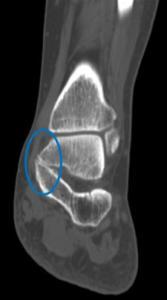

Tarsal koalisyon, ayak kemiklerinin gelişimi sırasında oluşan bir ayrışma anomalisidir. Bu kemikler arasındaki birleşme fibröz doku, kıkırdak veya kemikten oluşmuş olabilir. Toplum içerisindeki görülme sıklığı %1 oranında bildirilmektedir ve olguların yarısında diğer ayakta da tarsal koalisyona rastlanır. En sık; talokalkaneal ve kalkaneonaviküler eklemler arasında koalisyon görülür.

Öykü ve fizik muayene yol gösterici olmakla birlikte ayak AP-Lateral ve oblik grafileri tanı açısından yardımcı olmaktadır. Doktorunuz cerrahi planlanmasında veya tanı açısından şüphe duyulması durumunda ise bilgisayarlı tomografi ve manyetik rezonans tetkiki ile detaylı inceleme yapmak isteyebilir.